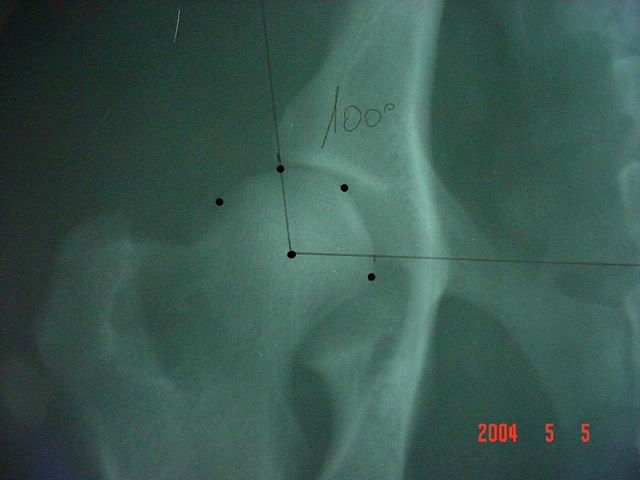

Kattintás=nagyításKözepes dysplasiánál a vápa sekély, a combcsontfej szögletes, az ízületi rés széles, illetve kiszélesedő, a fej a vápából fokozottan kilóg (90°-100°). Az ízületen és környékén osteoarthrosis jelei gyakran megfigyelhetőek.